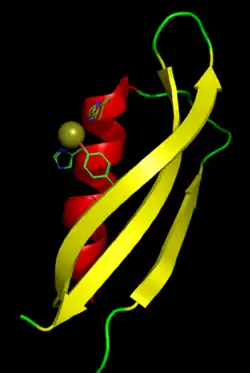

Structure

A number of different structural domains that fold mostly on their own have been found in the APP sequence. The extracellular region, much larger than the intracellular region, is divided into the E1 and E2 domains, linked by an acidic domain (AcD); E1 contains two subdomains including a growth factor-like domain (GFLD) and a copper-binding domain (CuBD) interacting tightly together.[24] A serine protease inhibitor domain, absent from the isoform differentially expressed in the brain, is found between acidic region and E2 domain.[25] The complete crystal structure of APP has not yet been solved; however, individual domains have been successfully crystallized, the growth factor-like domain,[26] the copper-binding domain,[27] the complete E1 domain[24] and the E2 domain.[23]